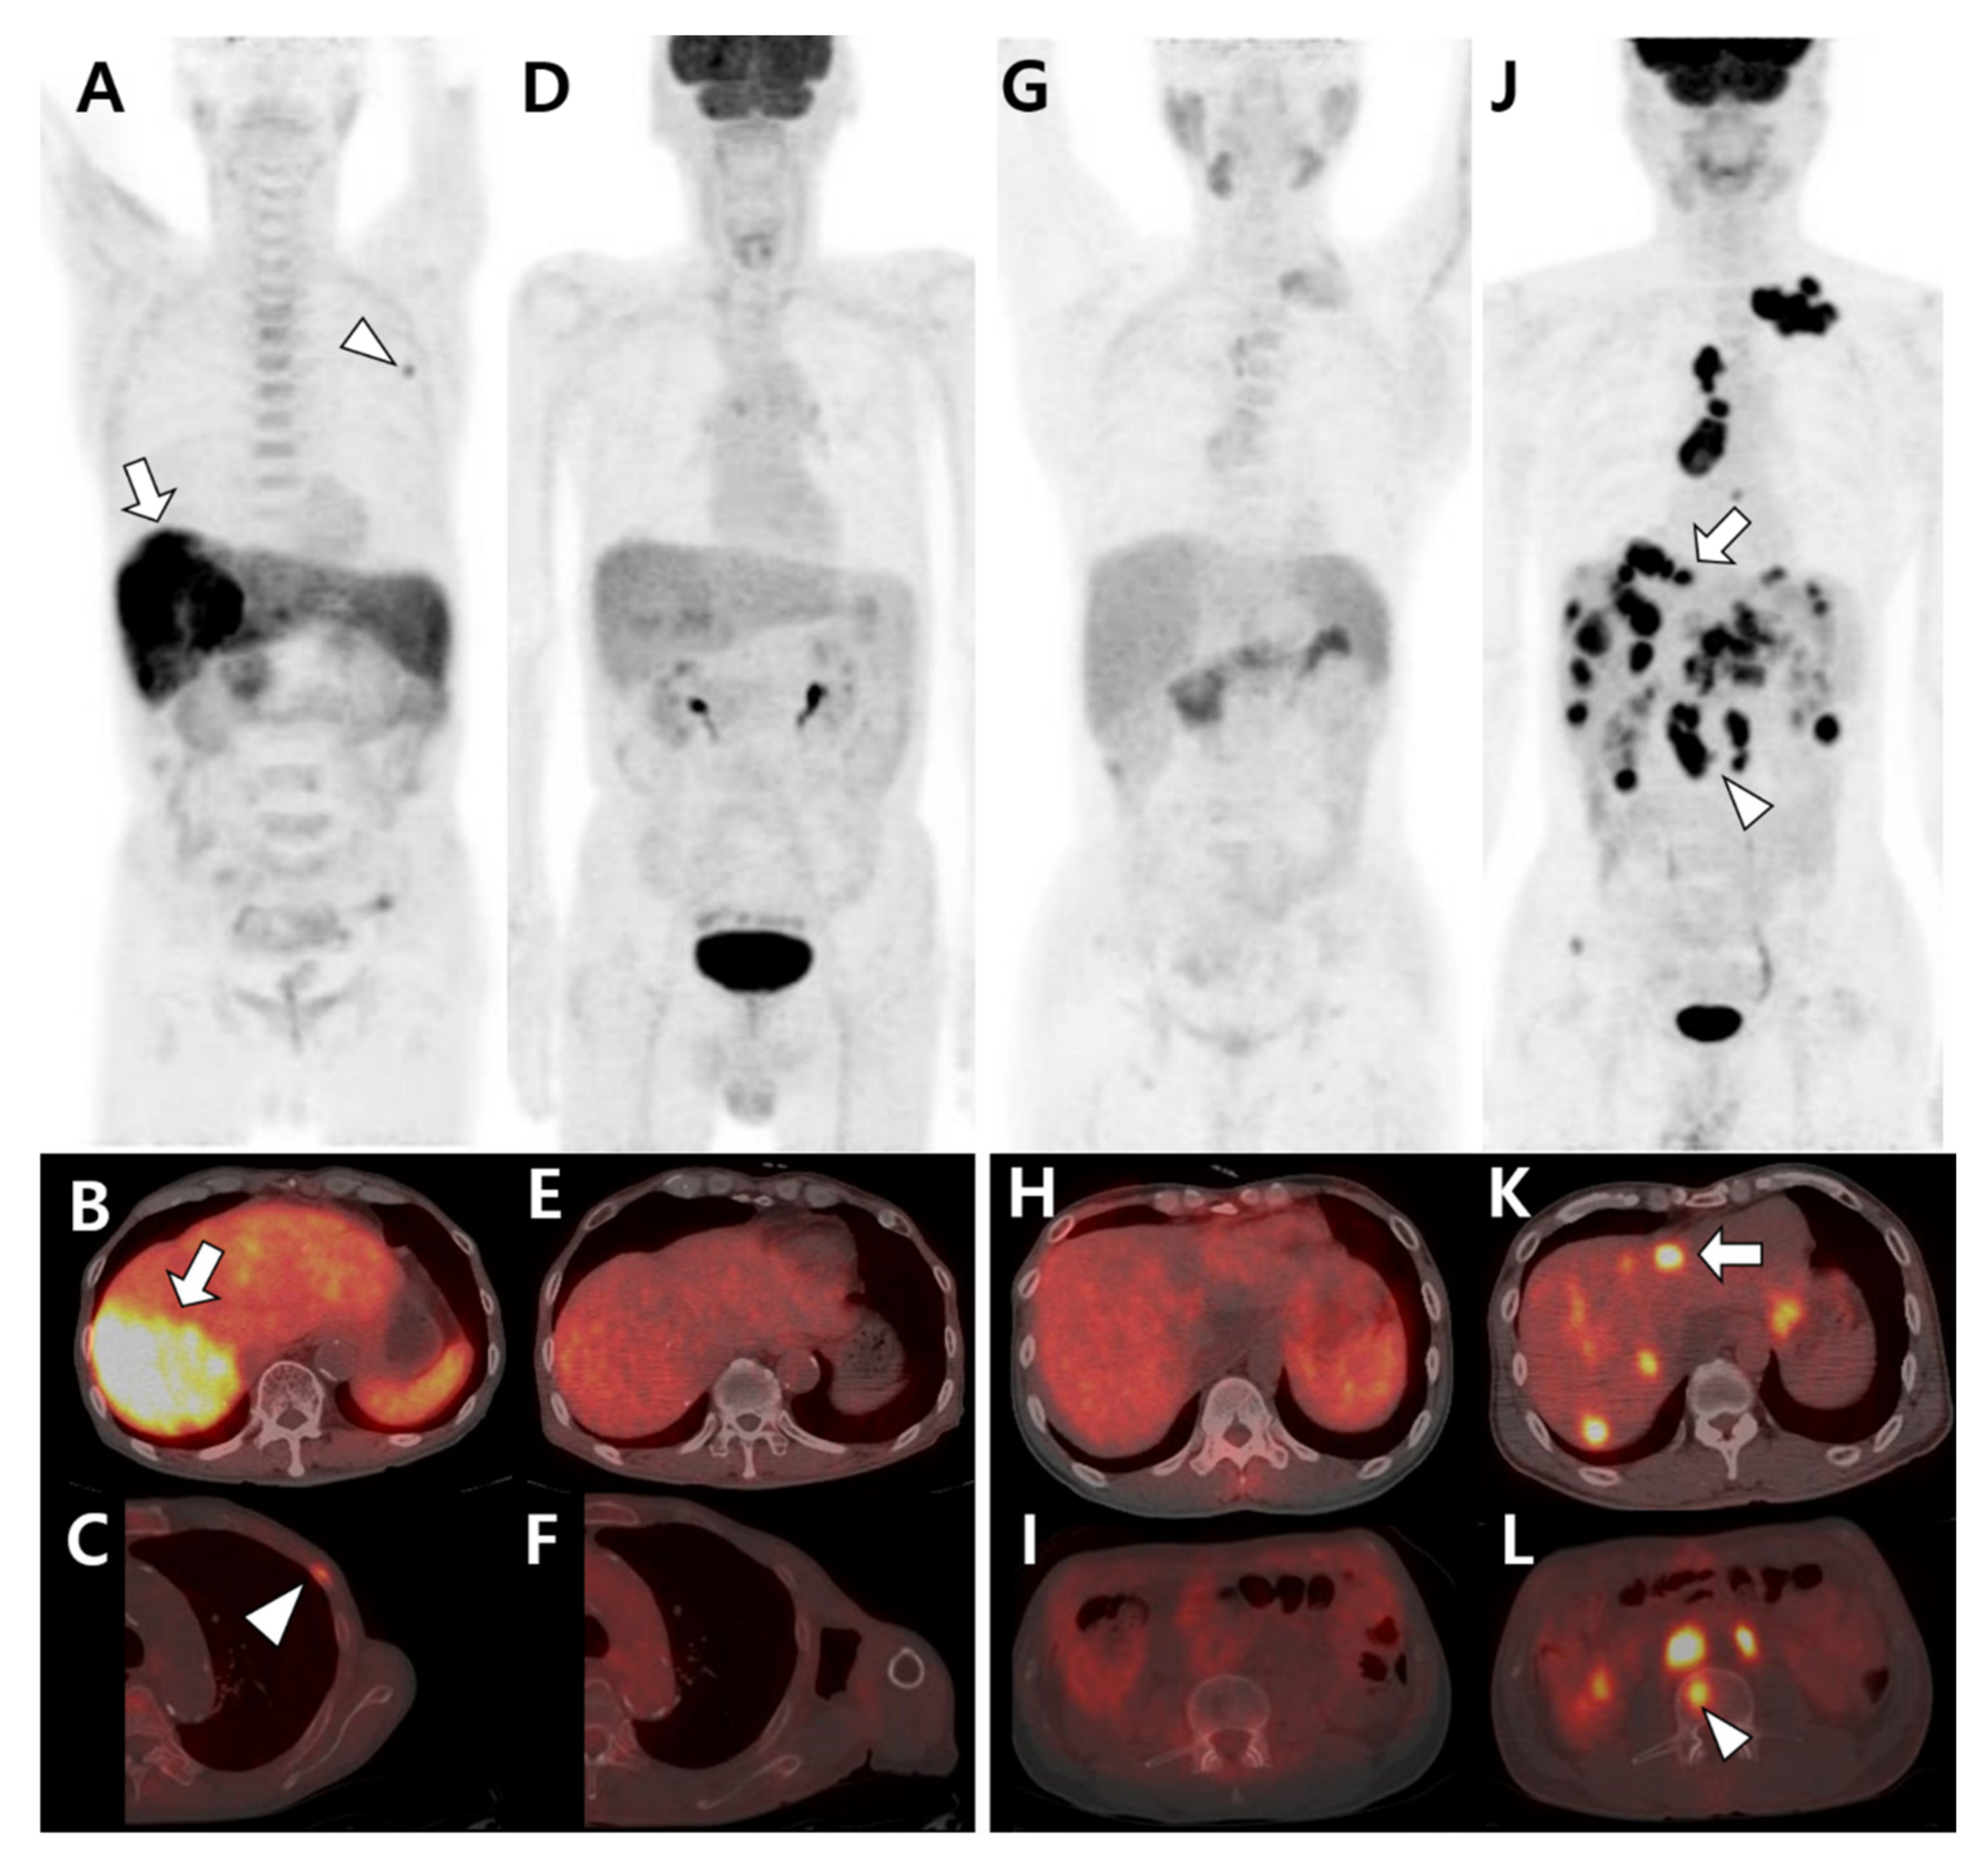

3.1. Multimodal Imaging According to the Primary Tumor Site and Histologic Type